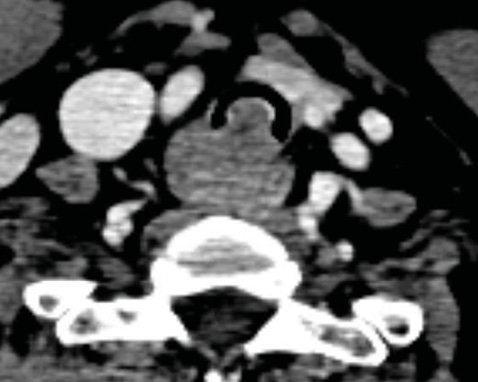

Пацієнтка віком 61 років звернулася зі скаргами на поступово прогресуючу задишку, сухий кашель та дискомфорт у ділянці дихальних шляхів. За результатами комп’ютерної томографії виявлено протяжне ураження трахеї. Ендоскопічне обстеження з біопсією підтвердило наявність аденоїдно-кістозної карциноми трахеї.

З урахуванням повільного, але інфільтративного характеру росту пухлини та її значної протяжності ухвалено рішення про радикальне хірургічне лікування. Виконано розширену циркулярну резекцію трахеї протяжністю 9 трахеальних кілець із формуванням первинного трахеотрахеального анастомозу. Досягнуто повної R0-резекції (рис. 4).

Рис. 4. Макроскопічний матеріал (протяжність резекції — 9 кілець)

Післяопераційний період: перебіг без клінічно значущих ускладнень. Пацієнтка перебувала під динамічним наглядом з регулярним ендоскопічним та променевим контролем. На момент останнього спостереження відмічено задовільну прохідність трахеї та відсутність ознак місцевого рецидиву.

Унікальність цього клінічного випадку полягає у протяжності резекції, що перевищує загальноприйняті межі, без розвитку анастомотичних ускладнень.